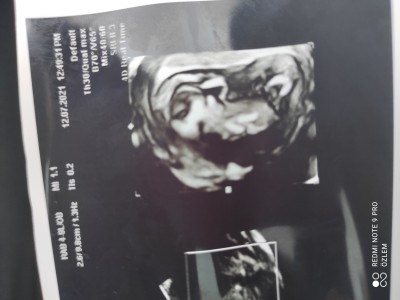

Hamilelik Dönemi Genel kategorisinde (7 puan)

14 haftalık hamileyim iki oğlum var kız istiyoruz ama nasip tahminleri alabilirmiyim dua edin

Gebelik haftası 14

Kapatılma nedeni: Cinsiyet tahminlerini sol üst köşeden konu dışı sohbetten sorabilirsiniz